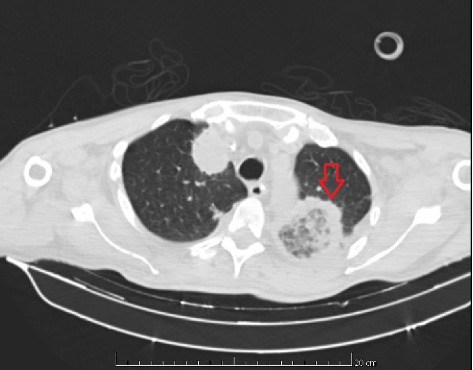

侵袭性毛霉病是一种侵袭性真菌感染,其特点是进展迅速,主要影响免疫功能低下的个体。在此,我们报告一例脾梗死合并胃肠道瘘和脑脓肿的病例,这是一种罕见的毛霉病活检的表现,在一名56岁的急性髓性白血病患者中得到证实。患者最初就诊时有3周的发热、盗汗和不适病史。考虑到胸部计算机断层扫描结果与真菌疾病和中性粒细胞减少症相符,他接受了广谱抗真菌治疗。在发生脾梗死和胃瘘后,患者接受了部分胃切除术和脾切除术。尽管采取了干预措施,但患者并没有取得成功的结果,并于术后第二天死亡。该病例强调了及时怀疑、立即抗真菌治疗和手术干预的重要性,以提高毛霉病多面表现患者的生存前景。

Invasive mucormycosis is an aggressive fungal infection characterized by rapid progression, primarily impacting immunocompromised individuals. Herein, we report a case of splenic infarction in association with gastrointestinal fistula and brain abscess as a rare presentation of mucormycosis biopsy, proven in a 56-year-old patient diagnosed with acute myeloid leukemia. The patient initially sought medical attention with a 3-week history of fever, night sweats, and malaise. Considering the chest computed tomography findings compatible with fungal disease and neutropenia, he underwent broad-spectrum antifungal therapy. Following the occurrence of splenic infarctions and a gastric fistula, the patient underwent a partial gastrectomy and splenectomy. Despite the interventions, the patient did not have a successful outcome and died on the second postoperative day. This case highlights the importance of timely suspicion, immediate antifungal therapy, and surgical intervention to improve the survival prospects of patients with multifaceted manifestations of mucormycosis.